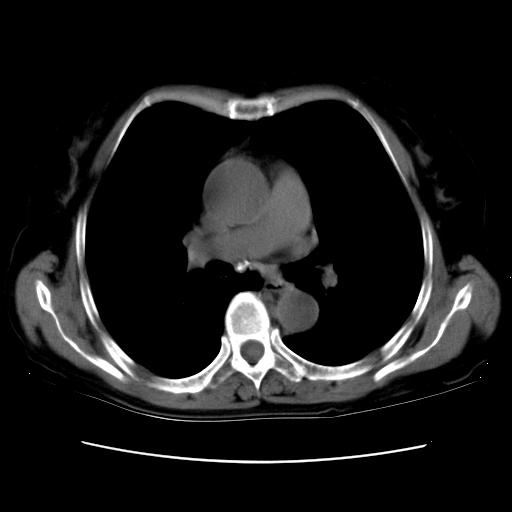

以下是引用卜一在2007-9-18 14:41:00的发言:[br]右肺肿块:毛刺+胸膜凹陷征+供血血管+浅分叶+强化。支持:周围性肺癌 !另:左侧甲状腺腺瘤!

以下是引用夏季在2007-9-18 11:00:00的发言:[br]1。右肺肿块,周围有短毛刺,肺门侧有血管与其相连,胸壁侧有胸膜凹陷征,考虑周围性肺癌 2。左侧甲状腺软组织肿块,内有高密度钙化灶,考虑左侧甲状腺腺瘤。